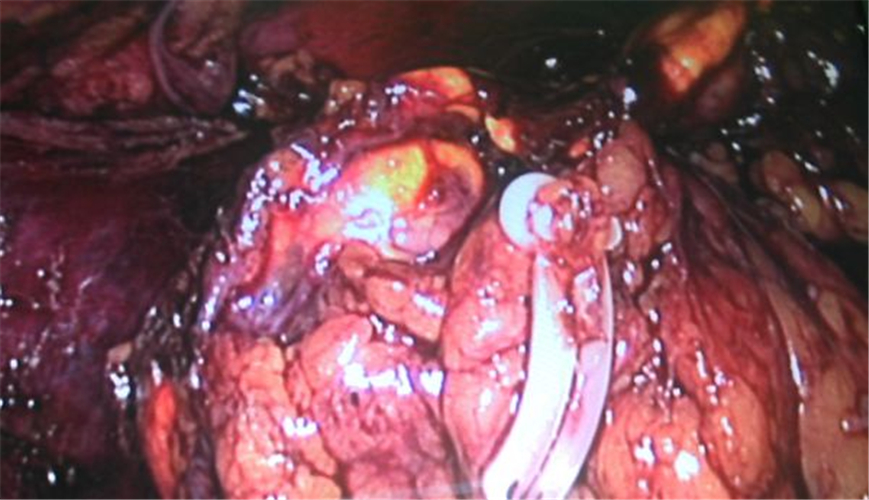

左側腎上腺腫瘤手術

右腎上腺腫瘤部分位於靜脈後

右側腎上腺腫瘤復發切除

右側腎上腺腫瘤手術中的

手術治療腎上腺腫瘤

腎上腺惡性腫瘤的“噩夢”—腹腔鏡下右腎上腺癌切除術